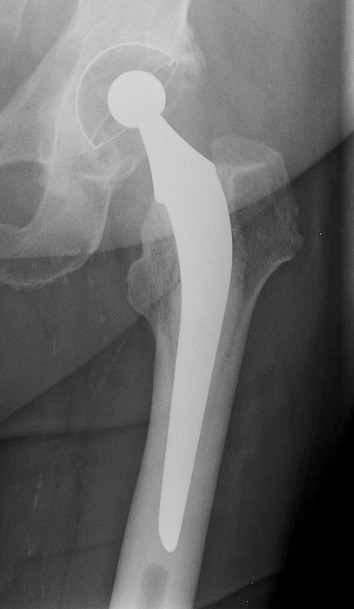

B. Prothèse de hanche avec céramique